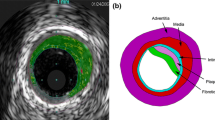

Atherosclerosis is a disease of arteries which commonly results in a reduction of lumen area, caused by a build up of fatty material in the artery wall, and a corresponding decrease in blood flow through the diseased artery. Common treatments for these stenosed arteries include balloon angioplasty, stenting or a combination of the two. The objective of these procedures is to increase the lumen size through mechanical loading of the stenosed artery. Little is known, however, about the inelastic mechanical behavior of atherosclerotic plaques and its contribution to lumen gain. A number of authors have investigated the response of atherosclerotic plaques to different loading regimes.3,11,18,22,23,27,28,42 The characterization of the response to mechanical testing has most commonly been undertaken using hyperelastic material models to describe the effects of monotonic uniaxial loading.28 To the author’s knowledge, Topoleski and coworkers42,43 are the only researchers to report specifically on the inelastic behavior of atherosclerotic plaques. In this study, the response of the plaques to successive cyclic compression loading regimes and successive stress relaxation loading regimes, with unloaded “rest” periods in each case, was investigated. The degree of recovery in the mechanical properties during the “rest” periods was found to depend on the plaque type, with calcified plaques reported as behaving more elastic than other types. However, further mechanical testing is needed to characterize atherosclerotic plaque response adequately for use in finite element (FE) analyses; in particular the inelastic behavior needs to be quantified across a wide range of applied strains in order to develop appropriate inelastic material models.

Cyclic compressive tests were performed on samples taken from plaques of the carotid bifurcation. Plaque specimens were removed from eight patients (five men and three women, 66.13 ± 9.13 years, mean ± SD) during routine carotid endarterectomies. All surgeries and tests were performed in the Galway Clinic, Ireland. The study includes 21 compressive samples obtained from eight carotid plaques. Table 1 includes all patient and lesion details. Plaque classifications were determined independently by a clinician using routine Duplex ultrasound with gray scale imaging.33,41 Ethical approval for testing of the human tissue was obtained prior to commencing this study from the Galway Clinical Ethics board.

Plaque specimens were prepared for testing immediately following removal in surgery. Specimens were dissected at the bifurcation, separating them into common, internal and external carotid segments as described in Maher et al.28 Each segment was opened by cutting along the axial direction. 4-mm diameter cylindrical radial compressive samples were removed from each of the flat rectangular segments using stainless steel punches. Testing samples were allowed to equilibrate in 0.9% saline solution for approximately 30 min before measurements of the sample dimensions were recorded.

Unconfined cyclic compression tests were performed on cylindrical compressive samples. A sample was placed on the lower platen and the upper platen was moved to apply a small compressive pre-load of 0.01 N to the sample at a crosshead speed of 0.001 mm/s. This ensured a consistent contact between the platen and the top of the sample and minimal strain in the plaque, <5% in all cases. The sample height was then taken as the distance between the platens at this pre-load. Loading was under strain control and several strain levels were applied with five loading–unloading cycles for each loading level. Samples were loaded and unloaded at a rate of 5% strain/s. The loading levels were between 10 and 50% strain in 10% increments and unloading was to the 0% strain level in each case, see Fig. 1. This testing methodology is similar to that used to determine stress softening in rubbers.24,47 Preliminary testing was performed on porcine arterial tissue in an attempt to rule out possible visco-elastic or poro-elastic response of the tissue. A resting period of 2 h at 0% strain was added every five cycles before the peak strain value was increased. No significant difference was found between the levels of inelastic deformation on unloading between arterial samples tested with or without the relaxation period present. This indicates that no significant recovery of the tissue occurred which suggests that the inelastic response was in line with the theoretical concept presented here.

The diameter of the samples used for mechanical testing was of a similar order of magnitude to the inhomogeneity observed in the tissue using both duplex ultrasound imaging and macroscopic visual observation. However, due to the resolution of the imaging used it is possible that smaller inhomogeneities such as micro-calcifications were not identified. Therefore, the test data provides global tissue mechanical properties specific to the local clinical classifications that can be made using duplex ultrasound.